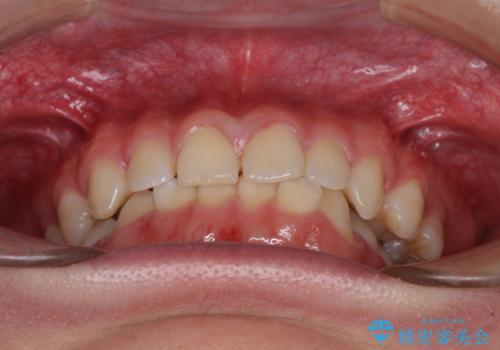

隙間とデコボコを治したい ワイヤー装置による矯正治療

- 前歯のデコボコと隙間を気にして来院された患者様です。

治療手段としてはワイヤー装置でもインビザラインでも可能でしたが、インビザラインの自己管理は自信がないとのことで、ワイヤー矯正により隙間を閉じていくこととしました。

隙間の原因は舌の突出癖であったので、舌癖改善のためのトレーニングを指導しながら治療を進めて行くこととしました。